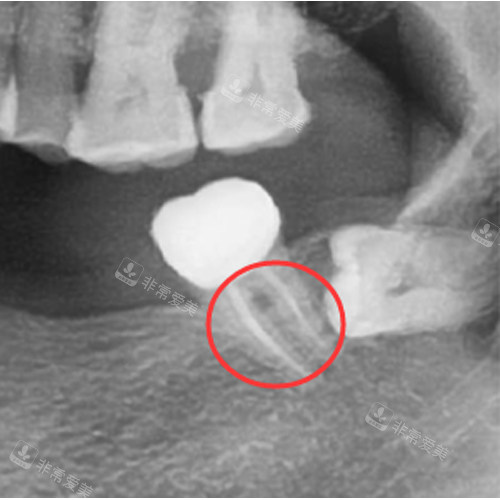

根管治疗过程示意图

根管治疗改善图

适合做根管治疗的情况

根管治疗后的牙齿